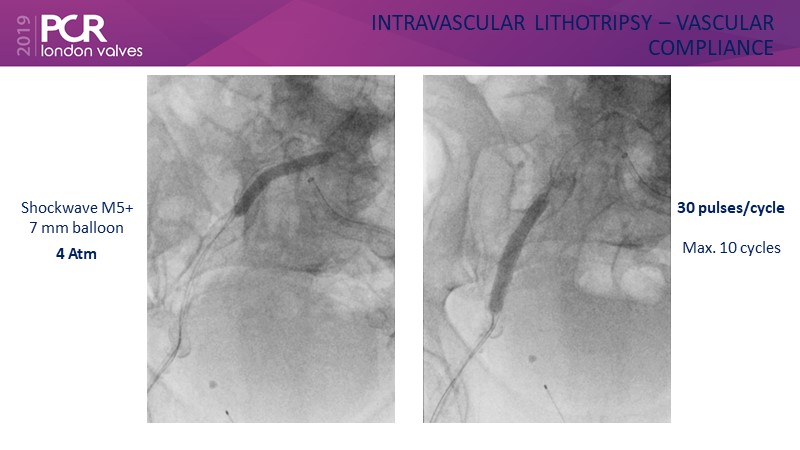

Transfemoral TAVI access using intravascular lithotripsy in patients with challenging peripheral vascular disease

- To understand how the unique mechanism of action of intravascular lithotripsy changes vessel compliance and mitigates procedural risk

- To hear the data supporting the safety and efficacy of intravascular lithotripsy in peripheral vessels